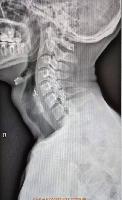

В случае перелома шейки бедра компания МосРентген Центр госпитализирует в Склиф для эндопротезирования.